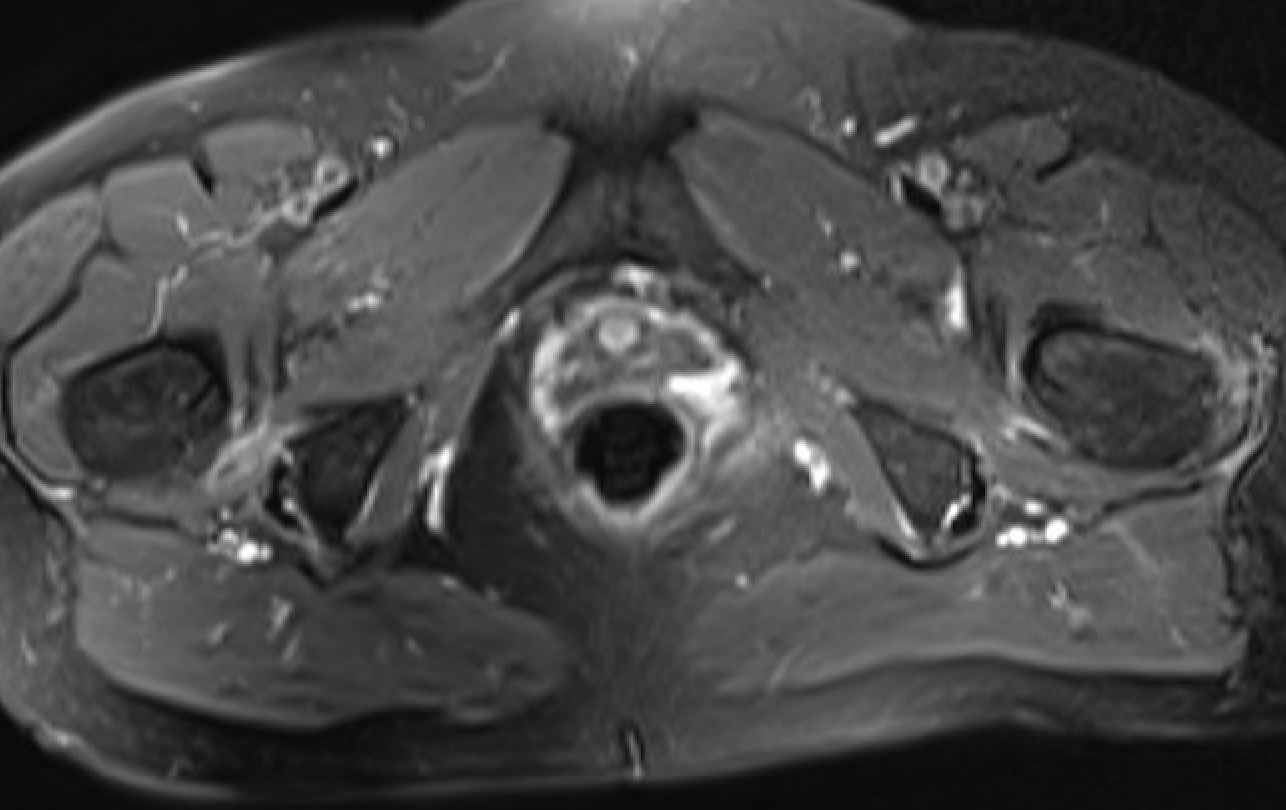

MRI

Reduced ischiofemoral space - distance between the lesser trochanter and the ischial tuberosity

Reduced quadratus femoris space - distance between hamstring tendon and iliopsoas

Inflammation / edema in quadratus femoris +/- fatty degeneration

Singer et al Skeletal Radiol 2015

- systematic review of 190 hip MRI of patients with ischiofemoral impingement

- compared to controls

- ischiofemoral space < 15 mm: sensitivity  77%, specificity 81%, accuracy 78%

- ischiofemoral space < 10 mm: sensitivity 79%, specificity 74%, accuracy 77%.